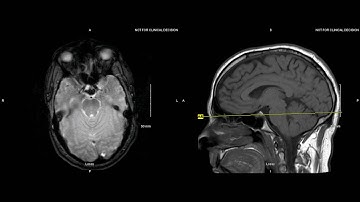

Unremarkable Non-Contrast CT Axial Bone Window-Example 3